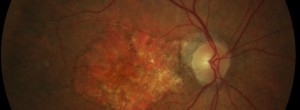

CHROMA: Ensayo Clínico de Lampalizumab en pacientes con atrofia geográfica secundaria a DMAE

Fase III Estudio de Lampalizumab en pacientes con atrofia geográfica secundaria a DMAE

MPL4 GA: Estudio Fase I en pacientes con atrofia geográfica secundaria a DMAE atrófica